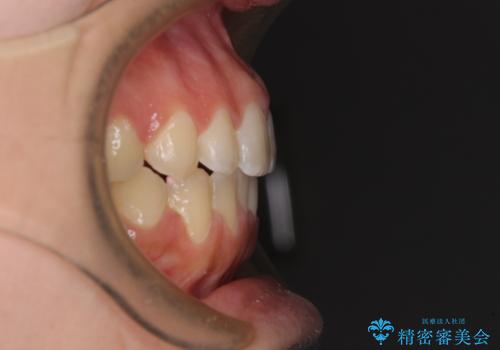

【モニター】オープンバイトをインビザラインで矯正治療

- 前歯の上下スペースによる食べにくさを気にして来院された患者様です。

インビザラインにより上下の前歯の隙間を閉じていくこととしました。

前歯のデコボコの解消と並行して上下の奥歯を圧下させるようにすることで、前歯を接触させるように計画しました。

上下の隙間に舌が入り込むことがオープンバイトの原因であったため、舌の筋肉のトレーニングも並行して行い、後戻りの抑制を図りました。